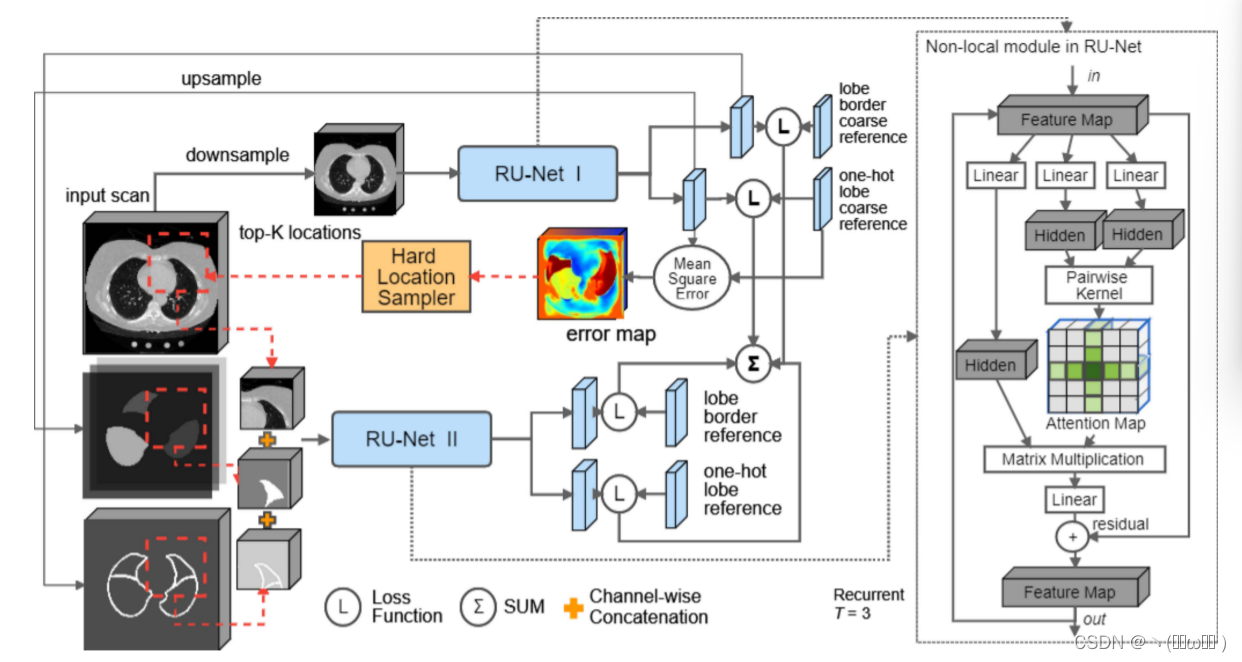

我们将叶分割问题定义为体素分类问题。 给定扫描 I,目标是预测每个空间位置 i 的体素标签 l^i,其中 l^i ∈ 标签集 L ={0, 1, 2, 3, 4, 5} 表示背景,左上,左下 、右上叶、右下叶和右中叶。 在本文中,我们使用具有两个级联 CNN 的多分辨率方法来捕获叶分割的全局上下文和局部细节,如 [15] 中所提出的。 我们的框架如图 1 所示。除了使用多分辨率框架外,我们还引入了一种新颖的非本地模块来捕获结构化关系,并且我们高效的网络设计允许对我们的多分辨率框架进行端到端训练。 对于每个 CNN,我们放置我们提出的非局部模块以最粗略的分辨率聚合特征的关系信息,因为这些特征通常表示高级语义,例如对象和对象部分 [34]。 所提出的非局部模块计算这些特征之间的视觉和几何对应关系,自然地建模对象和对象部分之间的关系。 几何信息的使用受到 [14] 的启发。 此外,所提出的非局部模块可以扩大这些特征的感受野,因为一个非局部响应的计算涉及特征图中的所有特征。 我们将在每个阶段都带有提议的非本地模块的 CNN 称为关系 U-Net (RU-Net),详细信息将在本节后面进行解释。

图1:具有两个 CNN 级联的叶分割框架的概述。 在每个阶段,CNN(RU-Net)使用提出的非局部模块来捕获对象和对象部分之间的结构化关系。 RU-Net I 的输出与裁剪的 3D 补丁连接,作为 RU-Net II 的输入。

1.级联关系U-Net

第一个RU-Net以下采样分辨率读取输入扫描,以粗略分割波瓣和波瓣边界。随后通过三线性插值将这些粗输出上采样到更高的分辨率。高分辨率输入扫描和第一个RU-Net的输出被串联并裁剪成3D补丁作为输入,以训练第二个RU-Net精确分割瓣和瓣边界。两个关系u网的级联是端到端训练的,允许在相同的优化过程中学习本地细节和扫描级上下文。此外,我们使用在第一个RU-Net的预测中发现的错误来最佳地采样3D补丁以训练第二阶段,这鼓励第二个RU-Net专注于第一个RU-Net失败的区域。这种技术可以看作是在线硬示例挖掘的一种形式。[35]。

2.关系U-Net

关系U-Net体系结构 (RU-Net) 是3D U-Net体系结构 [24],具有较少数量的卷积滤波器和额外的非本地模块。RU-Net在编码路径中有三个下采样层,每个层由两个卷积和一个最大池化操作组成。沿着下采样路径,再使用两个卷积将卷积滤波器的数量增加一倍。然后,我们在向上采样之前放置非本地模块。在上采样路径中,使用三层来重建分辨率,每个层包含一个三线性插值,然后是两个卷积以减少插值伪影。最后,通过两个并行输出分支中的单个1 × 1卷积来重塑特征,每个特征对应于不同的学习目标; 一个人产生6通道softmax概率,用于分割背景和五个瓣。另一个通过sigmoid函数提供单通道概率图,用于预测波瓣边界。对3 × 3卷积的特征进行批量归一化,并通过整流器线性单元 (Relu) 激活。不使用dropout。第一个RU-Net使用填充卷积,而第二个使用有效的卷积。表II中提供了有关两个阶段的RU-Net网络体系结构的详细信息,其中下采样层的名称以 “下” 为前缀,而上采样层的名称以 “上” 为前缀。列出的数字基于执行顺序。

如图 1 所示,使用红色虚线,我们计算第一个 RU-Net 的 lobe-wise softmax 概率与 lobe 参考标准之间的均方误差 (MSE)。 然后我们遍历所有滑动窗口 3D 补丁,找到 MSE 积分最高的 K 个补丁,并将它们用于训练第二个 RU-Net。 K 设置为 1.0,以便在开始时使用所有补丁进行训练并不断减少,直到在训练过程结束时它仅覆盖大约 20% 的扫描体积。 所提出的在线硬样本挖掘不会在网络上引入额外的前向和后向传播,因此额外的计算成本是微不足道的。